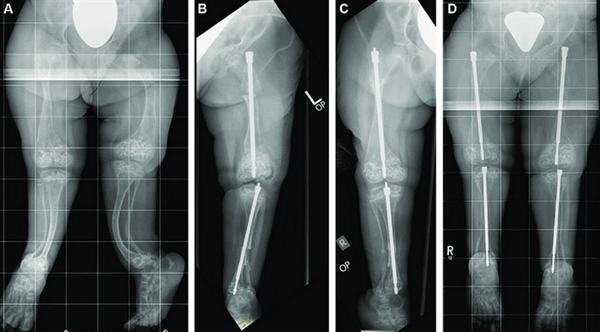

Корригирующие остеотомии (пересечение кости) с одномоментной коррекцией деформации (без удлинения) и фиксацией (при помощи ортопедических имплантов);

Коррекция деформации и удлинение конечностей методом Илизарова. Для этого выполняется остеотомия, устанавливается чрескостный аппарат. Удлинение осуществляется путем ежедневного дозированного изменения длин резьбовых стержней между кольцевыми опорами чрескостного аппарата

Мы используем кольцевые и полукольцевые чрескостные аппараты (типа Илизарова). Устранение деформации (в конце периода удлинения), в большинстве случаев, осуществляется при помощи узла на базе компьютерной навигации Орто-СУВ (гексапод).

1 цикл - параллельное удлинение и коррекция деформаций обеих голеней;

2 цикл - перекрестное удлинение и коррекция деформаций бедро- голень;

3 цикл - перекрестное удлинение и коррекция деформаций бедро-голень (противоположных).

Цикл составляет от 6 месяцев до 1 года. Между циклами - перерыв не менее1 года.Между первым и вторым циклами удлинения нижних конечностей - удлинение плеч.Повторное удлинение плеч (при необходимости) после 3-его цикла удлинения нижних конечностей.

В ряде случаев алгоритм может включать в себя 4 цикла:

2 цикл - параллельное удлинение и коррекция деформаций обоих бедер;

3 цикл - параллельное удлинение и коррекция деформаций обеих голеней;

4 цикл - параллельное удлинение и коррекция деформаций обеих голеней.